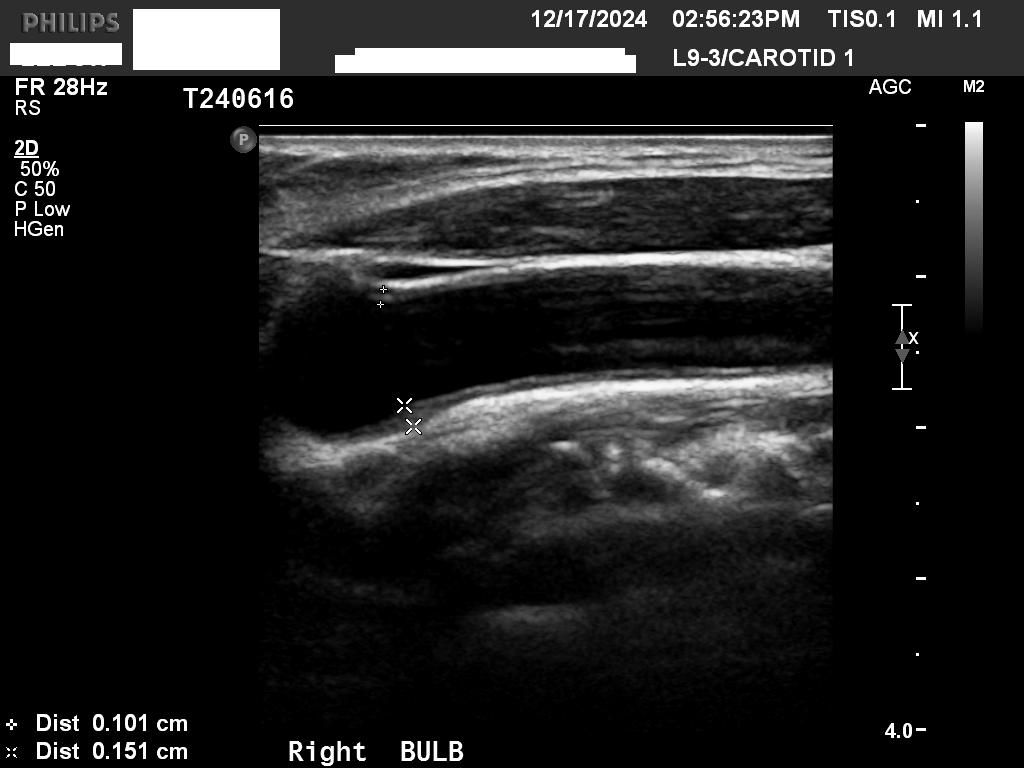

• 2번 째 사진

일반적으로 IMT가 1mm 보다 두꺼운지를 확인하고 혈관에 플라크가 있는지를 봅니다

초음파 사진으로만 보면 동맥경화가 경증으로 있는 것 같습니다